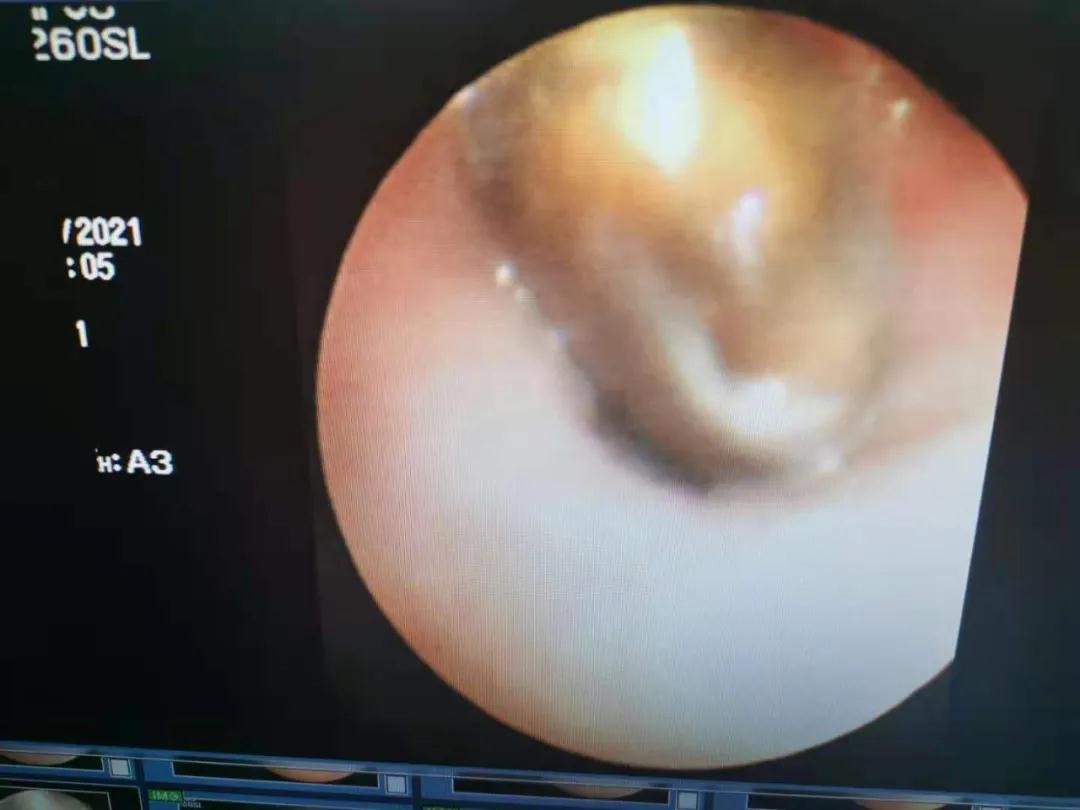

既然已经确定异物,取出异物是根本解决办法。术前准备就绪后,边鹏为牛牛做了内镜下支气管镜异物取出手术。

术中边鹏发现,在牛牛右肺下叶三级亚段支气管内,有一枚不足1厘米大小的西瓜籽。

3分钟后,边鹏利用钳夹顺利把西瓜籽取出。